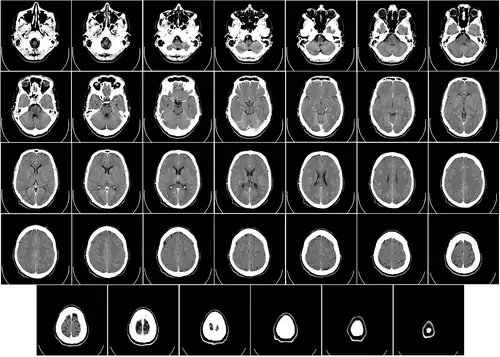

Головной мозг человека занимает почти всю полость мозгового отдела черепа, кости которого защищают головной мозг от внешних механических повреждений. В процессе роста и развития головной мозг принимает форму черепа.

Строение головного мозга

Объём мозга большинства людей находится в пределах 1250—1600 кубических сантиметров и составляет 91—95 % ёмкости черепа. В головном мозге различают пять отделов: продолговатый мозг; задний, включающий в себя мост, мозжечок и эпифиз; средний; промежуточный; и передний мозг, представленный большими полушариями. Наряду с приведённым выше делением на отделы, весь мозг разделяют на три большие части:

Половые различия

Мозг взрослого мужчины в среднем на 11—12 % тяжелее и на 10 % больше по объёму, чем женский[19][20], что соответствует разнице в массе и размерах тела у полов. Статистической разницы между соотношением размеров тела и мозга у мужчин и женщин не обнаружено[5][21]. Методы томографического сканирования позволили экспериментально зафиксировать различия в строении головного мозга женщин и мужчин[22][23]. Установлено, что мозг мужчин имеет больше связей между зонами внутри полушарий, а женский — между полушариями. Данные различия в структуре мозга были наиболее выражены при сравнении групп в возрасте от 13,14 до 17 лет. Однако с возрастом в мозге у женщин количество связей между зонами внутри полушарий возрастало, что минимизирует ранее отчётливые структурные различия между полами[23].